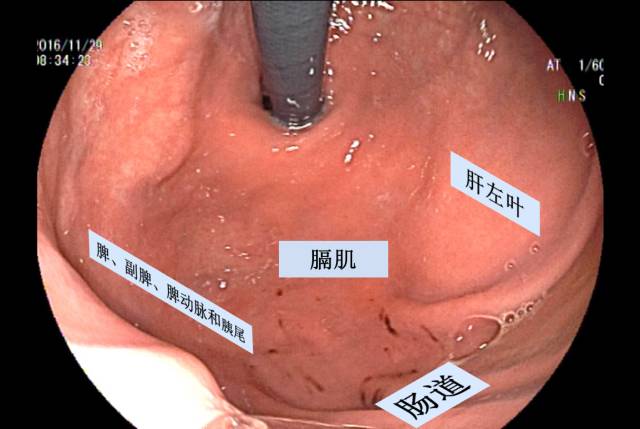

高位胃体前壁在右侧与肝左叶贴近,在左侧与膈相邻,胃后壁与胰、横结肠、左肾和左肾上腺相邻,胃底与膈和脾相邻。胃腔注气扩张后,来源于上述脏器的病灶对胃壁形成压迫,表现为向胃腔内突出的半球形隆起,光镜下与SMT难以鉴别。在介绍相关典型病例前,我们一起熟悉胃壁外压图。

接着,我们来看看下面的典型病例。